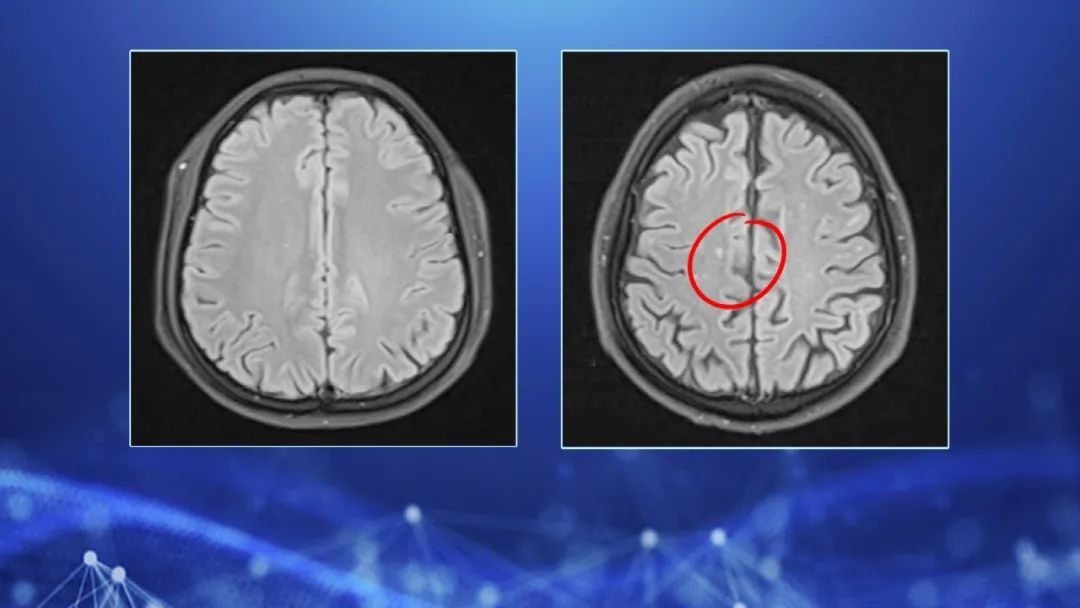

说到头疼,大家都不陌生,不少老年人都会有头疼的问题,反反复复持续很长时间,大部分人都不觉得是个大问题,但是今天节目却来了一位特别的患者,这位徐阿姨遭遇了让她崩溃的头疼,而且这一疼就是将近30年,吃了大概1万粒的止痛药也没有缓解,她曾经怀疑自己是不是出现了梗塞或者是肿瘤,走遍了多个科室,反复的检查都没有明显的问题,一直到了2016年,徐阿姨的检查中发现大脑局部有缺血症状,甚至有点地方有梗死灶,原来,在悄然间徐阿姨已经悄悄的脑梗了。